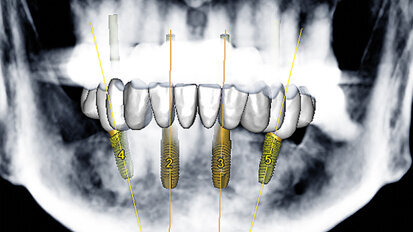

Dynamická navigace pro přesnou implantaci v případech kritické anatomie

Při použití CBCT snímku coby mapy, řídí dynamická navigace chirurgy stejně jako GPS navigace řidiče. Lékař si virtuálně naplánuje, kam by ...